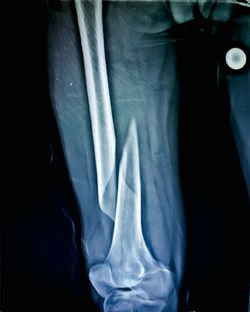

7月、母親は特養へ入所。大腿骨骨折した父親は現在も入院中だ。